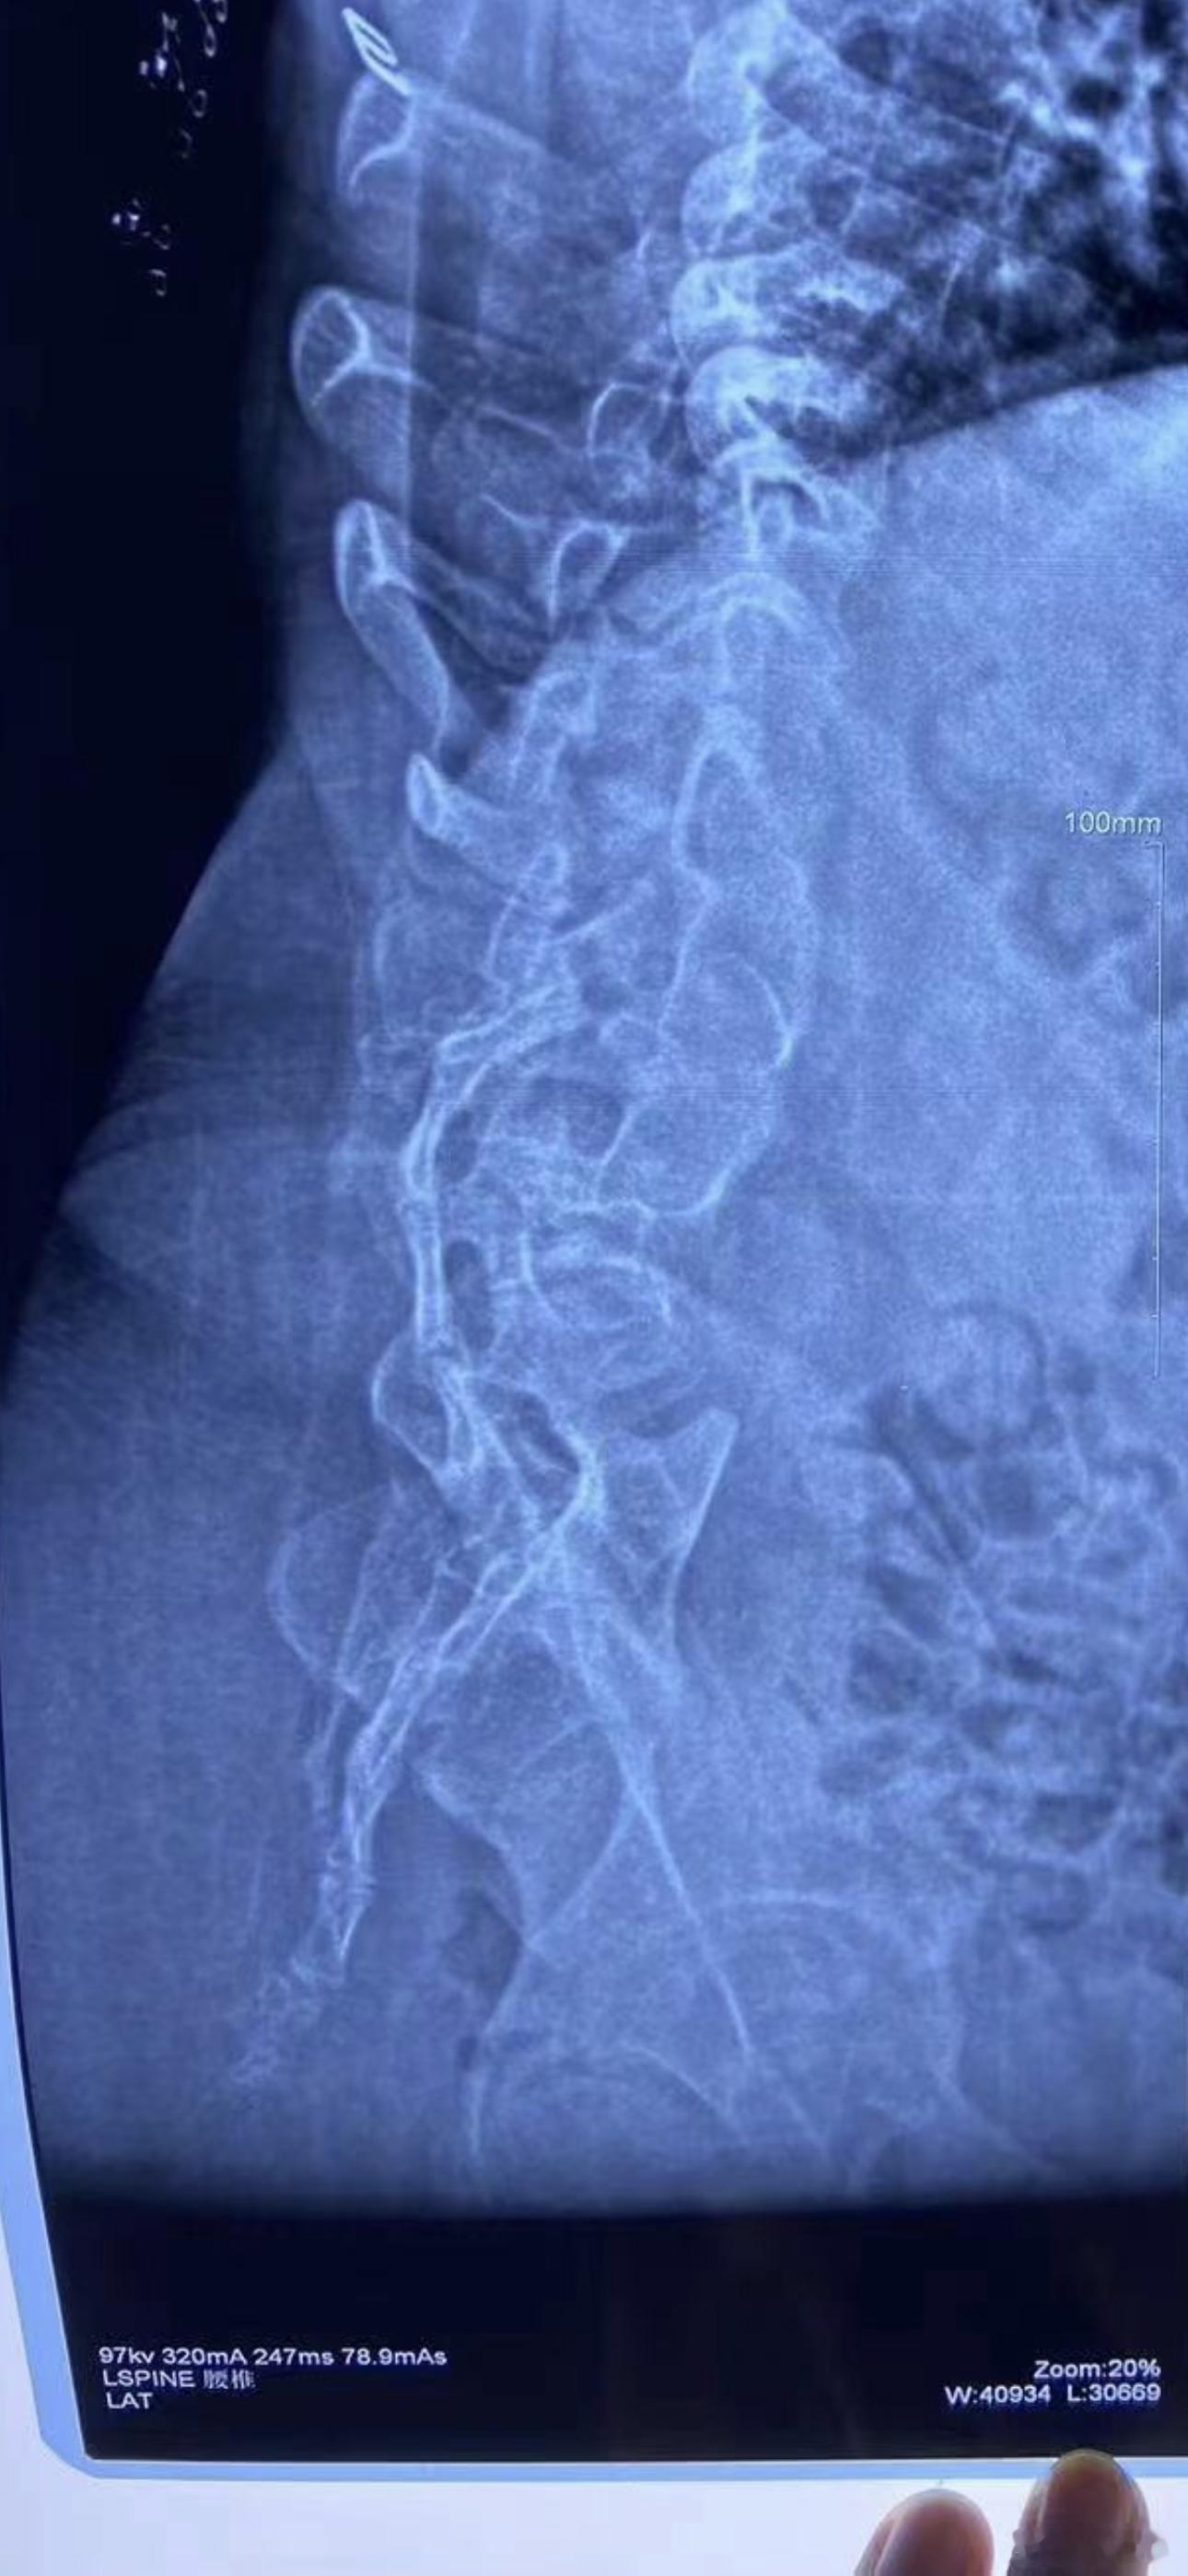

这是一位严重的先天性脊柱裂脊膜膨出大小便障碍女性,併有严重侧突、后突、底尾椎异位,双肾返流积水。她丈夫也脊膜膨出大小便障碍是我近20年前(2007年)用肖氏手术治愈,大小便完全正常。这些年他一直想为其妻也作肖氏手术,可怜两个残疾人实在太贫穷凑不够钱。去年10月,我院宣佈对残疾人肖氏手术免费,遂得以行肖氏手术,和双侧抗返流手术。现已能自主排尿,双肾积水基本消失。顺便说一句:这俩口子都是平顶山人,肖氏手术最早是在平顶山煤矿总医院成功,我一直心存感激,我要是早知道这女孩是平顶山人,早给她免费手术了。